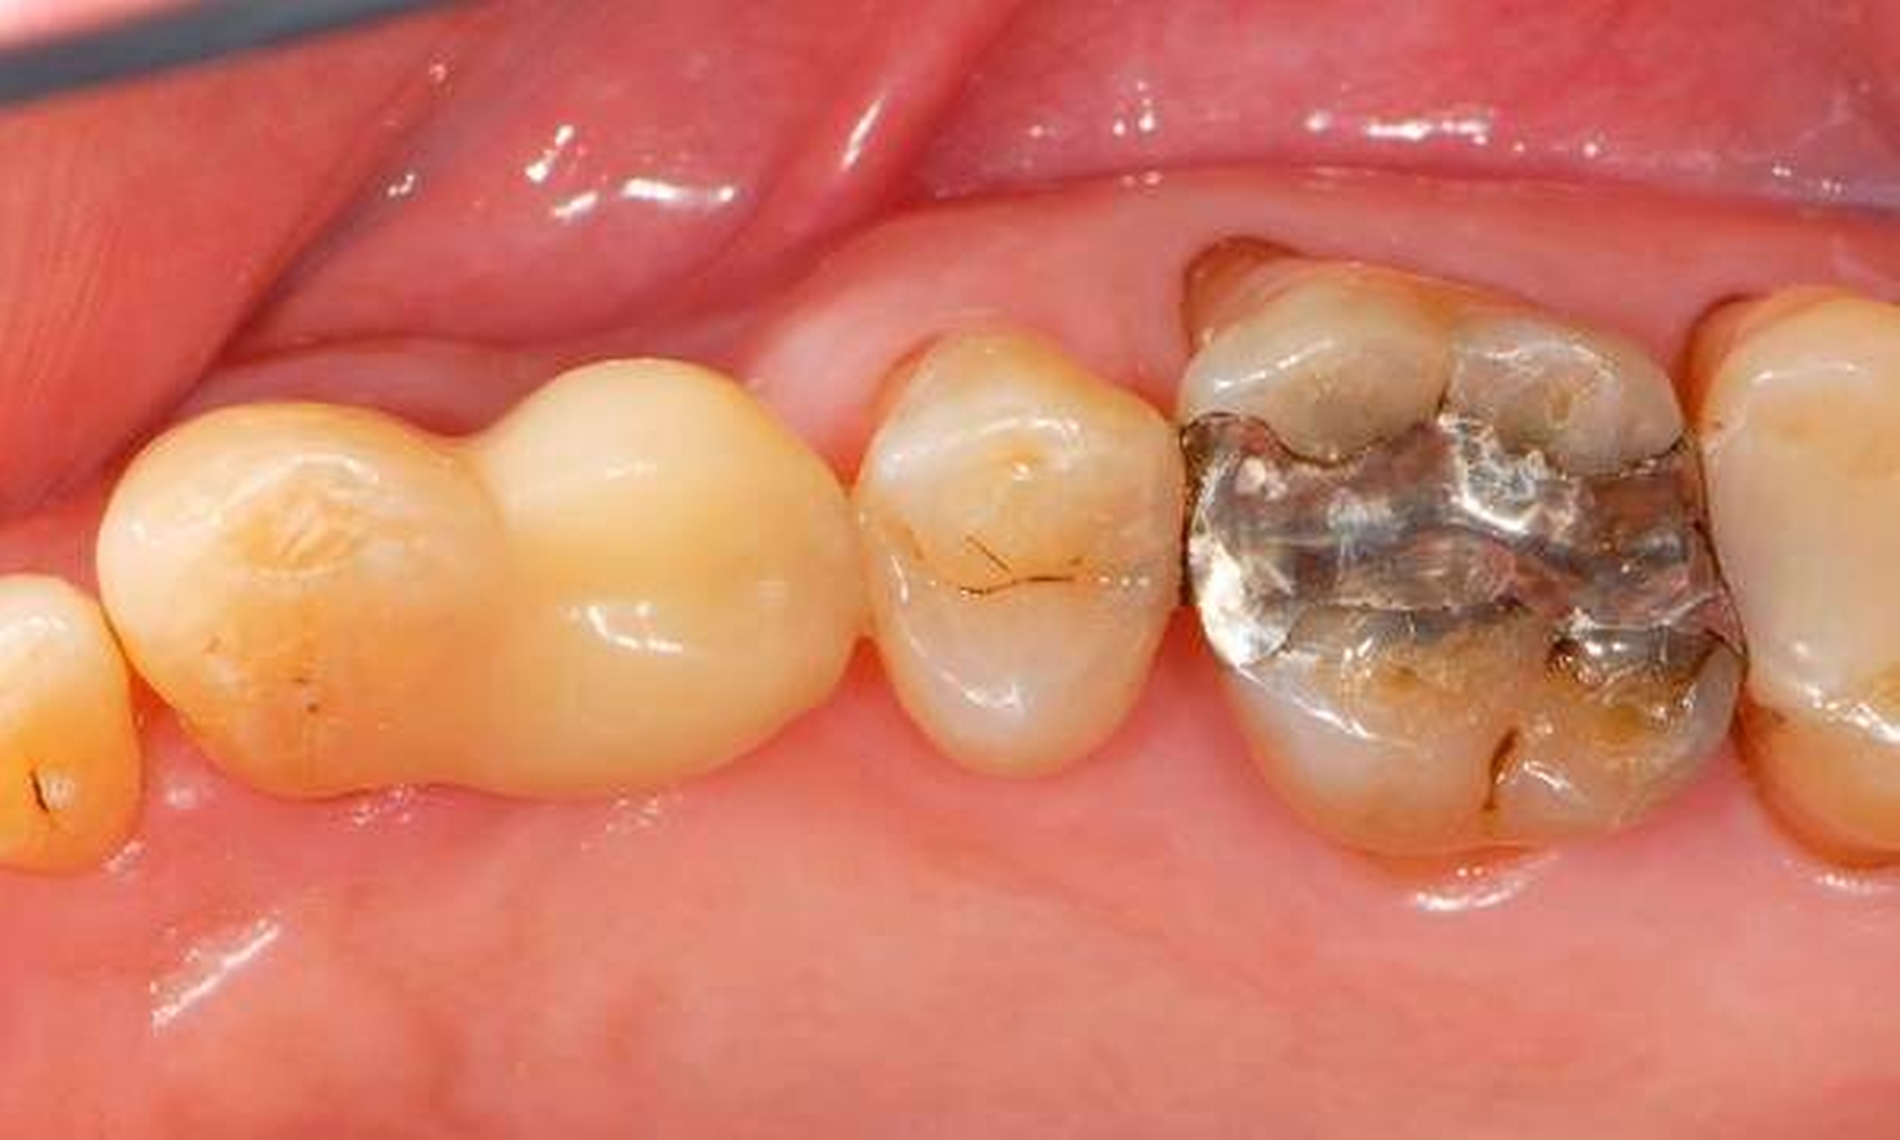

Wenn man die die Zahnmedizin betreffenden direkten und indirekten Werbeaktivitäten von Industrieunternehmen beobachtet, fällt auf, dass zwei Bereiche dominieren und zwar nicht nur im Hinblick auf PR-Maßnahmen aller Art für die Profession, sondern auch für die Bevölkerung. Zum einen handelt es sich um umfangreiche Aktivitäten zur Steigerung von Implantatversorgungen, zum anderen um die Verkaufsausweitung elektrischer Zahnbürsten. In beiden Fällen wird oftmals der Hightech-Charakter herausgestrichen. Unter bestimmten Versuchsbedingungen schneiden elektrische Zahnbürsten zwar etwas besser ab als Handzahnbürsten. Sichtet man allerdings die Literatur genauer, ist man gut beraten, mit der Interpretation vorsichtig zu sein. Ganß schrieb dazu in einer aktuellen Übersichtsarbeit zum Thema „Zähneputzen – Mythen und Wahrheiten“: „Die Überlegenheit elektrischer Bürsten gegenüber Handzahnbürsten konnte bislang nicht nachgewiesen werden“ [Ganß, 2016]. Bedenklich erscheint es, wenn Hersteller elektrischer Zahnbürsten suggerieren, man könne mit diesen Hilfsmitteln die Interdentalräume suffizient reinigen. Dies ist nämlich nicht ganz korrekt. Viele Menschen benötigen besondere zusätzliche Hilfsmittel zur Interdentalraumhygiene, wobei individuelle Instruktions- und Trainingsmaßnahmen unabdingbar sind. Da diese oftmals nicht in Anspruch genommen werden (können), verwundert es kaum, dass sich hier Effekte kaum aussagekräftig messen lassen.

Wenn beispielsweise ein Patient mit tiefen Zahnfleischtaschen Interdentalraumbürsten anwendet, die ohne nennenswerten Widerstand die Zahnzwischenräume passieren, kann man nicht erwarten, dass ihm dies zu einem großen Nutzen für die Zahngesundheit verhilft. Dies betrifft auch Implantatträger [Staehle et al., 2016]. In Abbildung 7 ist ein Patient gezeigt, der trotz Parodontalbehandlung und regelmäßiger Reinigung mit einer – zu dünnen – Interdentalraumbürste hohe Sondierungstiefen und Bluten nach Sondieren aufwies. Erst nach Umstellung auf eine größere Interdentalraumbürste mit längeren Seitenborsten und einem genügend hohen Passagewiderstand durch den Interdentalraum wurde der Taschenfundus mit den Borsten besser erreicht und es kam zu einem deutlichen Entzündungsrückgang.

Eine zahnmedizinisch sinnvolle frugale Intervention für viele Menschen wäre, ihnen eine Handzahnbürste zu empfehlen und dies bedarfsgerecht durch geeignete Interdentalraumbürsten zu ergänzen. Dies wäre in manchen Fällen wesentlich besser, als jemanden durch die alleinige Empfehlung einer elektrischen Hightech-Zahnbürste in einer falschen Sicherheit zu belassen und auf Interdentalraumbürsten zu verzichten. Allerdings muss man einräumen, dass derzeit Interdentalraumbürsten relativ teuer und verschleißanfällig sind und dass das oft sehr unübersichtliche und unvollständige Produktangebot nicht den tatsächlichen Erfordernissen genügt. Insofern besteht hier auch von Herstellerseite Handlungsbedarf.